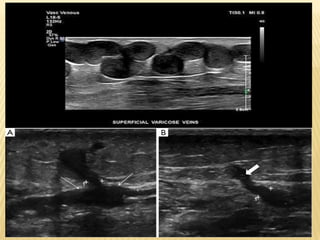

VARICOSE VEINS • Normalflow of blood in the venous syste depends upon the presence of competent valves, which prevent reflux. •Venous return is supplemented with contraction of the muscles in the lower limb, which pump the blood toward the heart. •When venous valves become incompetent they tend to place extra pressure on more distal valves, which may also become incompetent. •This conditionproduces dilated tortuous superficial veins (varicose veins) in the distribution of the great (long) and small (short) saphenous venous systems. Some individuals have a genetic predisposition to developing varicose veins. m